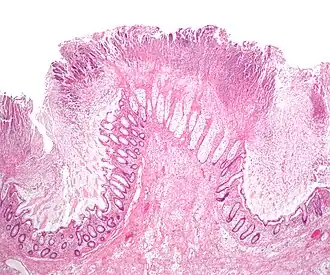

Anatomie pathologique

Lors de la coloscopie sont prélevées des biopsies de façon systématique au niveau des lésions pathologiques. L'examen histologique ne permet souvent pas de faire le diagnostic mais permet d'éliminer une pathologie concomitante ou un diagnostic différentiel. On observe ainsi des lésions de colite inflammatoire aiguë non spécifique. Plus spécifique, une nécrose superficielle de la muqueuse surmontée d'un enduit fibrinoleucocytaire et mucoïde permet d'évoquer fortement le diagnostic qui doit cependant toujours être confirmé par l'examen biologique des selles[6].